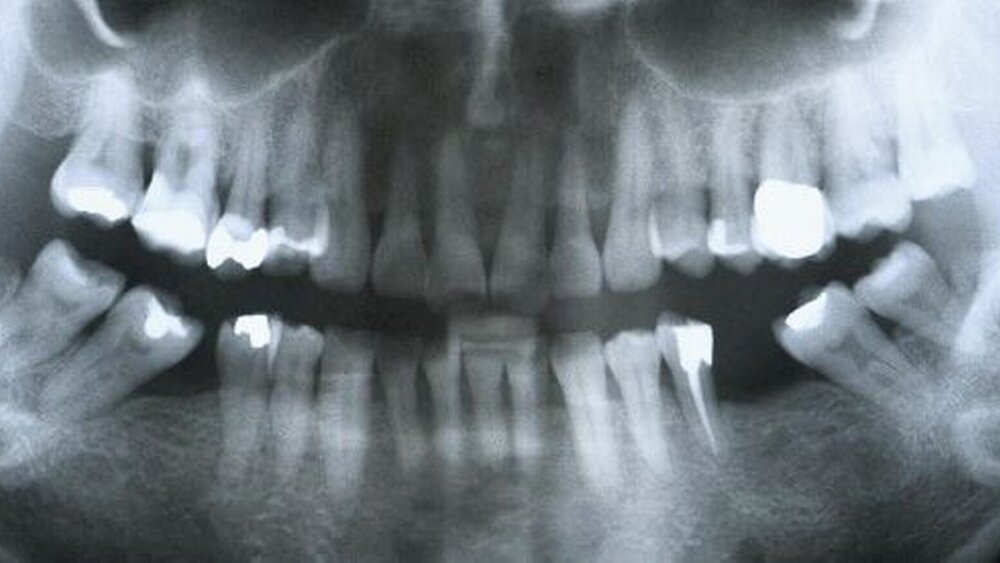

Bemerkenswert waren auch die äußerst kontroversen Einschätzungen zur Frage, wann ein prothetischer oder implantologischer Lückenschluss im Fall eines Zahnverlustes angezeigt sei. Aus endodontischer und parodontologischer Sicht wurde moniert, dass besonders in der implantologischen Literatur oftmals ein Lückenschluss vorgenommen würde, der die Fragen des medizinischen Nutzens bzw. der Nutzen-Risiko- Abwägung unter Berücksichtigung der Verhältnismäßigkeit des Mitteleinsatzes nicht hinreichend aufgreife. In diesem Punkt trafen – wie aus dem in der Abbildung präsentierten Beispiel hervorgeht – in Berlin fast unvereinbar erscheinende Positionen aufeinander: Eine gesunde 59-jährige Patientin, der im Alter von sechs Jahren die beiden Unterkiefermolaren 36 und 46 extrahiert worden waren, suchte zahnärztlichen Rat zu der Frage, wie man mit den beiden Lücken künftig verfahren solle. Die Ausdehnung der Lücken war durch Zahnkippungen verringert, rechts mehr als links. Die parodontale Situation war seit Jahren stabil (keine erhöhten Sondiertiefen, kein Bluten nach Sondieren), die vorhandenen Restaurationen wiesen keine Mängel auf, die eine Intervention nahegelegt hätten. Es konnte nicht auf funktionelle oder ästhetische Einschränkungen verwiesen werden. Während von endodontischer und parodontologischer Seite dafür plädiert wurde, vor dem Hintergrund der seit langer Zeit bestehenden Lücken die Situation zu belassen und zu beobachten, wurde vor allem von implantologischer Seite, zumindest auf der linken Seite, eine Implantatversorgung empfohlen, teils nach vorheriger kieferorthopädischer Zahnaufrichtung (siehe Tabelle).

Endodontologe

Kein Lückenschluss regio 036 & 046 erforderlich, da Lücken seit Langem bestehen

Parodontologe

Lücken belassen, auch keine restaurative Therapie, da aktuell nicht nur keine parodontalen, sondern auch keine ästhetischen oder funktionellen Probleme erkennbar sind; regelmäßige Kontrollen (einschließlich Situationsmodellen)

Implantologe I

Extraktion der Zähne 28, 38 & 48, anschließend KFO-Behandlung (Aufrichtung von 37 & 47, Lücken öffnen); Implantation in regio 036 & 046, ggf. mit Bone Spreading/Bone Splitting; 4 Monate später Freilegung mit bukkalem Verschiebelappen, Versorgung mit Titanabutment und Vollkeramikkronen

Implantologe II

Unterkiefer rechts: kein Lückenschluss regio 046 (nur Okklusions -ausgleich); Unterkiefer links: 35 & 37 Krone, 036 Implantat, okklusal adjustieren

Implantologe III

Unterkiefer rechts: do-Inlay bei 45 und mo-Inlay bei 47 mit flächen-hafter Berührung beider Inlays (bessere Reinigungsmöglichkeit mit Interdentalraumbürsten); Unterkiefer links: Implantat und Krone, zusätzlich bei 26 neue Krone und Okklusion in Idealkauebene

Prothetiker

Lücke 046: keine Therapie; Lücke 036: evtl. Versorgung unter Abwä-gung der Gefahr weiterer Zahnkippungen und Elongationen oder bei Auftreten funktioneller Einschränkungen der Patientin